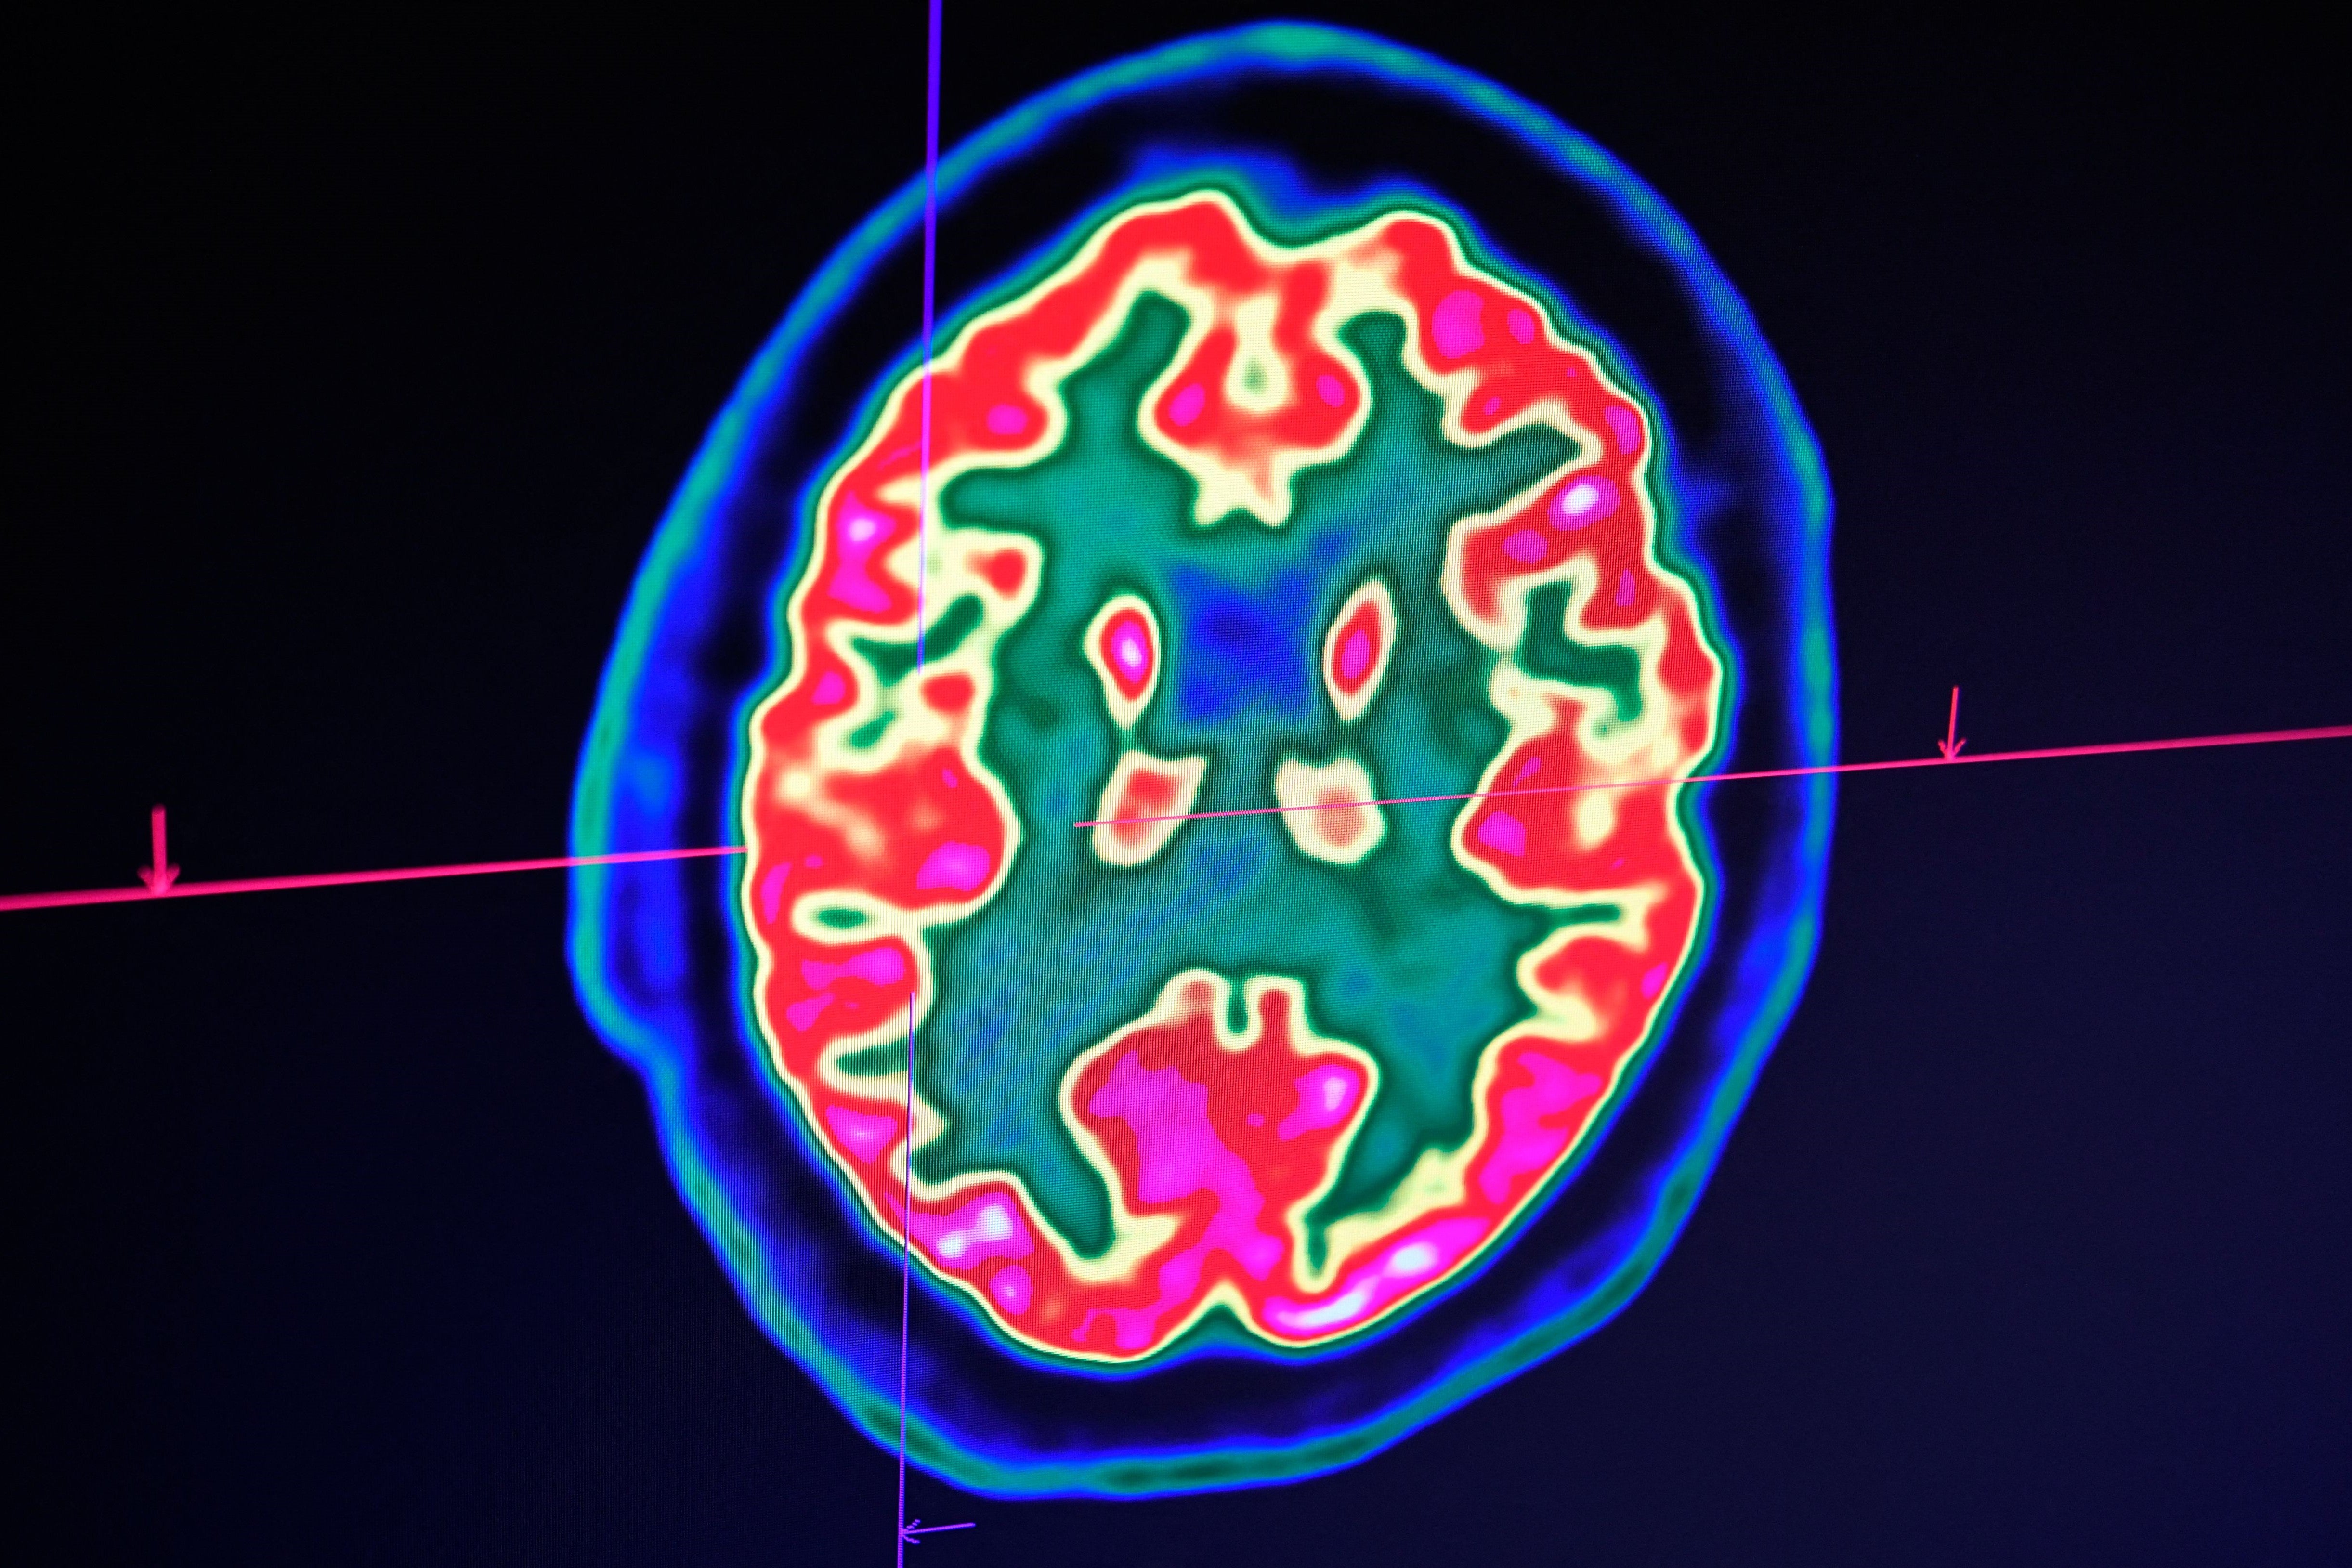

Researchers in China have discovered that AI models like ChatGPT process information in a similar way to the human brain.

The findings, made by a team from the Chinese Academy of Sciences and South China University of Technology, revealed that LLMs “share fundamental similarities that reflect key aspects of human conceptual knowledge” – challenging the assumption that AI systems simply mimic responses through pattern recognition.